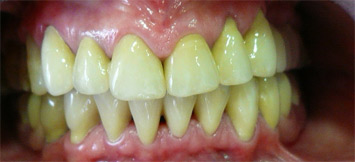

poslije